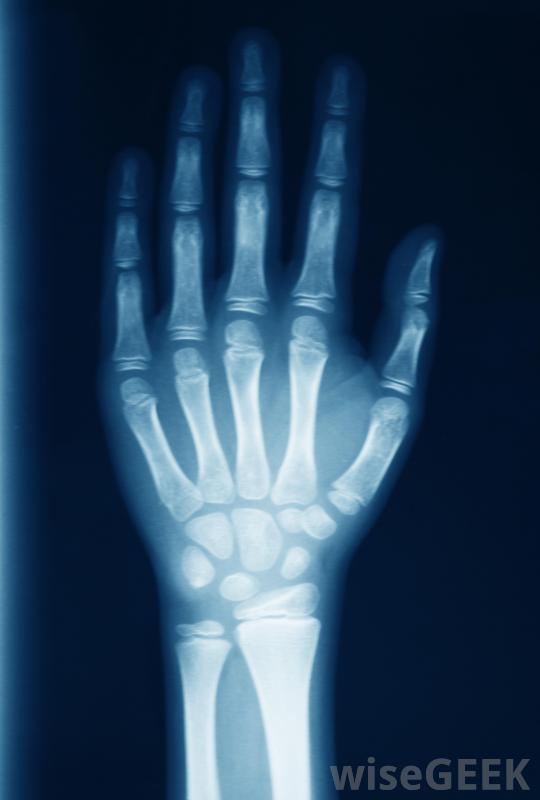

手指麻木最常見的原因是什么(Most Common Causes of a Numb Finger)?

可能導致手指麻木的原因很多。神經緊張、多發性硬化癥、凍傷、焦慮癥、腕管綜合征、低鉀水平和使用振動電動工具都會導致手指麻木。其他神經系統疾病也會導致手指麻木,但隨著時間的推移,這些通常會導致更廣泛的癥狀,麻木可能不是主要癥狀大多數手指麻木的癥狀都是良性的,可以治療。這取決于病情的嚴重程度,有些病因可能很嚴重,除非馬上治療。例如凍傷,最終會殺死手指組織,導致永久性損傷或截肢,如果有足夠的時間,通常會自行痊愈。用鍵盤打字會對手腕造成困難,可能會加重腕管問題并導致手指麻木腕管綜合征是導致手指麻木的最常見原因之一,它是一種由長期重復運動引起的病癥,尤其是當手腕或手的位置不正確時,使用電腦的人最容易患腕管,大多數情況下一個或多個手指會變得麻木,然后手和手腕會疼痛,有時還會腫脹治療方法包括戴上特制的支具,偶爾還要做手術。多發性硬化癥會導致手指麻木手指麻木的一些潛在原因是慢性的,通常會持續一生。多發性硬化癥(MS)等疾病最終會隨著時間的推移而惡化,并可能導致虛弱的癥狀。MS可能開始于手指、手、腿的麻木或刺痛,或者腳部。癥狀可能會從四肢向外擴散。為了控制癥狀,必須服用藥物,不適和麻木的緩解是很常見的。手指的麻木和刺痛可能會抑制個人執行基本任務(如刷牙)的能力大多數情況下,一個或多個手指的麻木并不是引起恐慌的原因。許多人認為這是一次性的。任何持續一兩天以上的麻木都應該由醫生檢查,以排除任何嚴重的健康狀況如果麻木伴有肌肉無力、疼痛、刺痛或無法控制的顫抖或震顫,尤其如此。凍傷會導致手指麻木雖然很少見,但也有嚴重的危及生命的神經系統疾病,開始時可能是手指麻木。這些疾病通常會迅速惡化,并可能導致永久性殘疾甚至死亡。Lou Gehrig病,或ALS,就是一個例子。通常會出現虛弱、抽搐、失去平衡和其他癥狀橈神經病變會導致手腕出現問題,也會導致手部部分麻木。手腕受傷可能導致手指麻木。